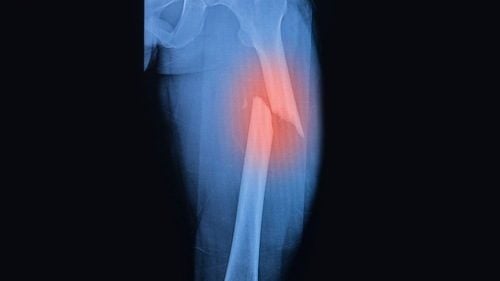

Chăm sóc bệnh nhân sau bó bột gãy xương

Bó bột là phương pháp kết xương trong gãy xương hiệu quả. Để người bệnh nhanh chóng hồi phục việc chăm sóc bệnh nhân sau bó bột gãy xương cần lưu ý những vấn đề sau. Gãy Xương Đòn Đeo Đai Số 8 Bao Lâu thì có thể Tháo được? Gãy xương chân kiêng ăn […]